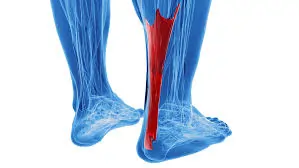

મોબિલિટી એક્સરસાઇઝ (Mobility exercises) આધુનિક ફિટનેસ અને રિહેબિલિટેશન (પુનર્વસન) દિનચર્યાઓનો એક આવશ્યક ભાગ બની ગઈ છે. ભલે તમે રમતવીર હોવ, ફિટનેસના શોખીન હોવ અથવા બેઠાડુ જીવનશૈલીને કારણે જડતાનો સામનો કરી રહ્યાં હોવ, તમારી ગતિશીલતા (mobility) સુધારવાથી તમારા જીવનની એકંદર ગુણવત્તામાં નોંધપાત્ર વધારો થઈ શકે છે. સાચા અર્થમાં ફક્ત સ્ટ્રેચિંગ કરવા કરતાં અલગ, મોબિલિટી એક્સરસાઇઝ સાંધાની…